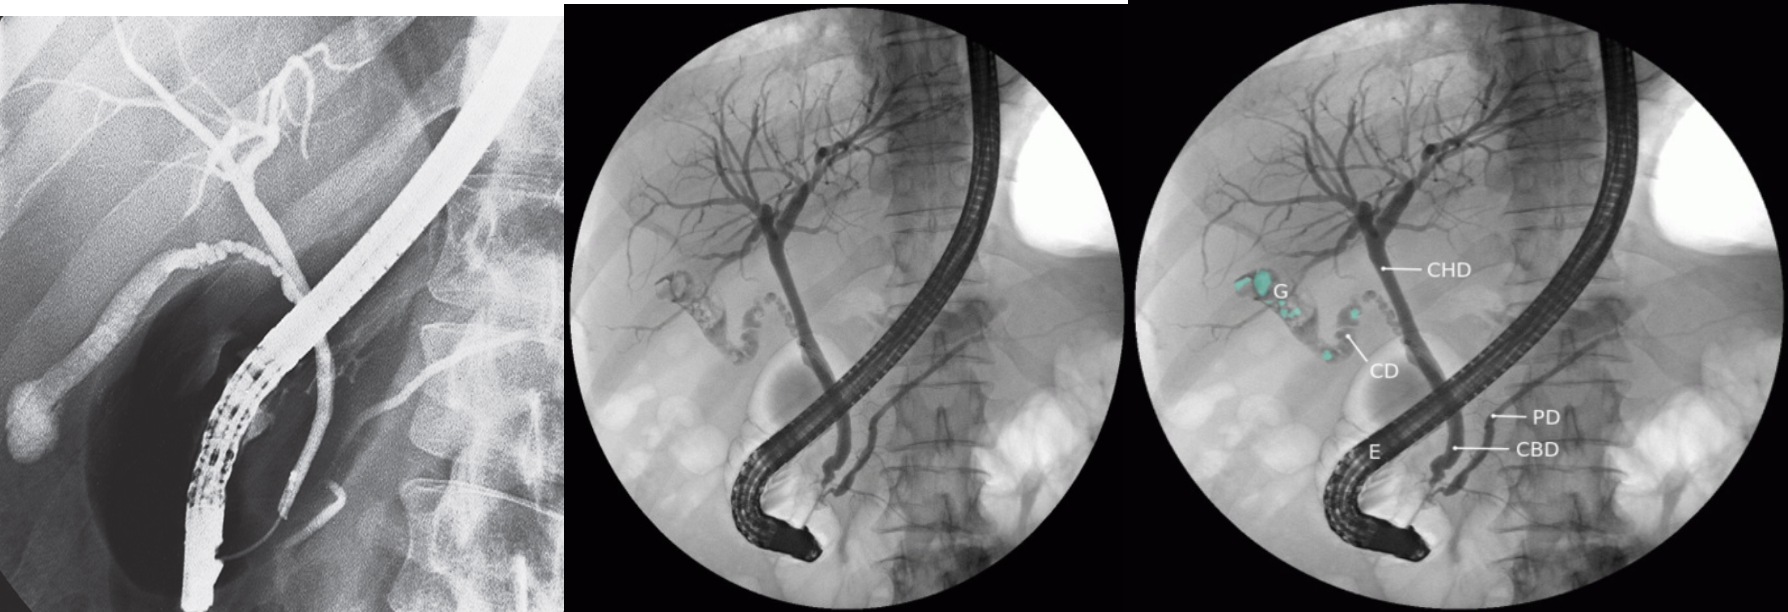

Endoscopic retrograde cholangiopancreatography (ERCP):

ERCP showing cholelithiasis (first image is normal)

Endoscopic retrograde cholangiopancreatography (ERCP) The tip of the endoscope (E) is located within the duodenum at the ampulla of Vater. Contrast enhancement allows visualization of the hepatic biliary tract, left and right hepatic ducts, cystic duct (CD), gall bladder (G), common bile duct (CBD), and pancreatic duct (PD), CHD: common hepatic duct. Multiple filling defects (examples indicated by green overlay) can be seen within the gall bladder and cystic duct.

This finding is diagnostic of cholelithiasis.